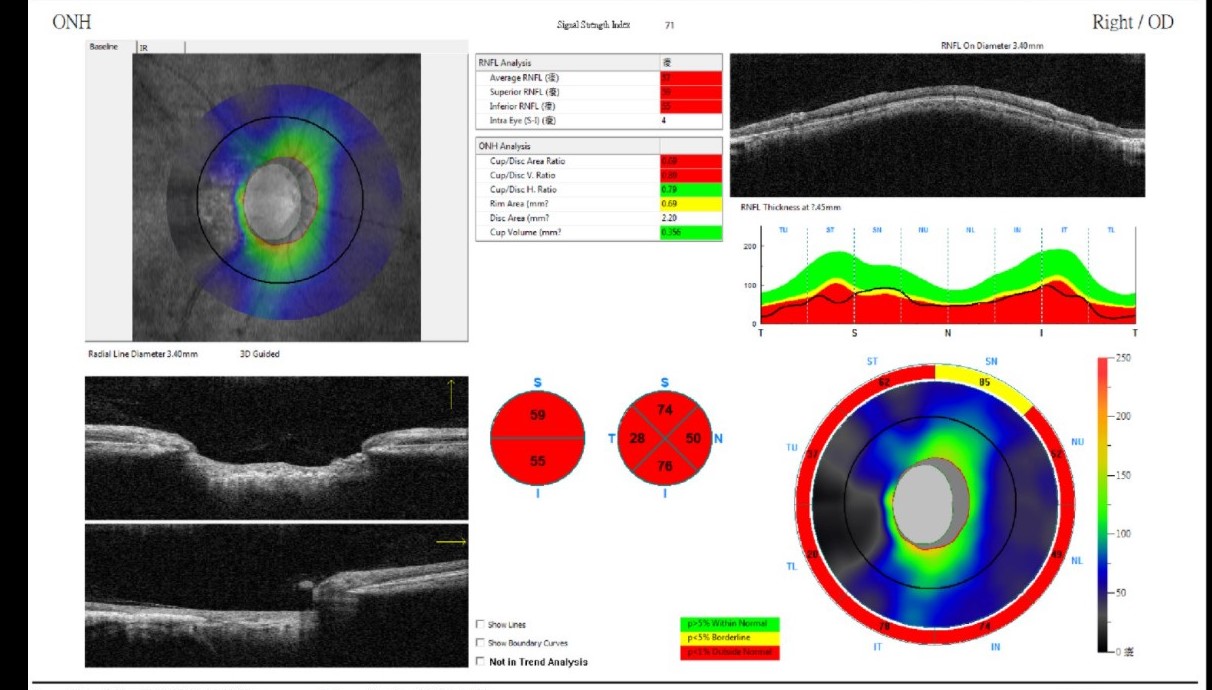

我最近因為視力模糊去醫院就醫,醫生幫我做了OCT及視野檢查,檢查如下。眼壓右眼21,左眼22。視力左右眼均650。目前醫生開了降眼壓的藥,我年紀40歲,長期使用電腦。請問檢查報告如何,有更積極的建議治療方式嗎?謝謝

右眼視野缺損比較多,且接近視力中心,這是你會感覺右眼視力模糊的原因,左眼還好算早期,眼壓21,22不算太高,算高眼壓型的青光眼,可能你的視神經較弱。

從現在開始要每天點藥降眼壓,讓視神經不受到壓迫,平時多做有氧運動,促進眼部微血管血液循環,也可以補充對眼睛有利的保健品,眼藥就是主要的知了方式,且降眼壓後視野缺損現象就會停止進展,但已受損的視神經,視野無法恢復,有氧運動,保健品為輔,能保養眼睛,增進視力,可參考